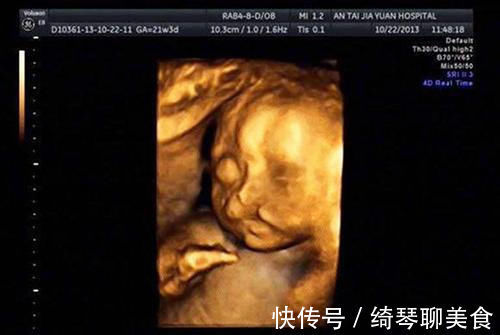

四维彩超,作为一个必不可少的孕检项目之一,也是孕期唯一一项能够提前看到宝宝模样的项目。所以,四维彩超对准妈妈和准爸爸来说也具有非常特殊的含义,不过有很大一部分孕妇表示:自己看完宝宝的四维彩超图都相当的失望。

品一品那些四维彩超图,简直就像在浏览印象派画家的得意之作,甚至有些胎儿拍出来的五官轮廓,连带有滤镜的亲爸亲妈都不能昧着良心说好看。

文章插图

别以为是宝宝天生就丑,事实上再好看的娃,在羊水里泡那么久也变得难看了。而且这个时候他们大多都是闭着眼睛,五官都还没有完全长开,所以拍出来丑一点也是情有可原的。